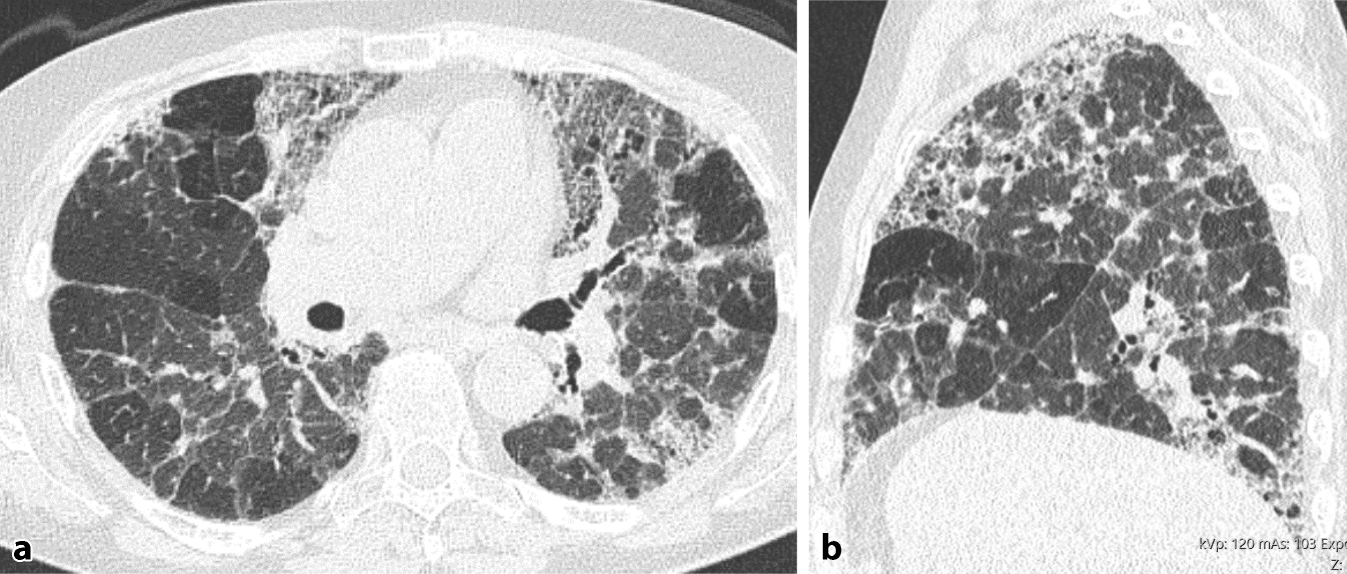

Abb. 3

Inflammatorische exogen-allergischen Alveolitis (EAA). a Axiale und b koronare multiplanare Reformation (MPR) einer nativen High-Resolution-Computertomographie (HRCT). Diffus in der Lunge verteilt zeigt sich eine Kombination aus Milchglas und Air-Trapping. Zeichen einer Fibrose fehlen